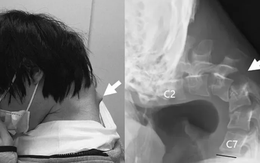

Thanh niên 25 tuổi mắc 'hội chứng cúi đầu' do nhìn điện thoại quá nhiều

Một người đàn ông Nhật Bản 25 tuổi dành phần lớn thời gian nhìn xuống điện thoại, cuối cùng không thể tự ngẩng đầu lên và được chẩn đoán mắc 'hội chứng cúi đầu'.